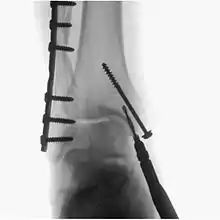

Surgical fluoroscopy

Fluoroscopy is used in various types of surgical procedure, such as orthopaedic surgery and podiatric surgery. In both of those, it is used to guide fracture reduction and in use in certain procedures that have extensive hardware.[5]